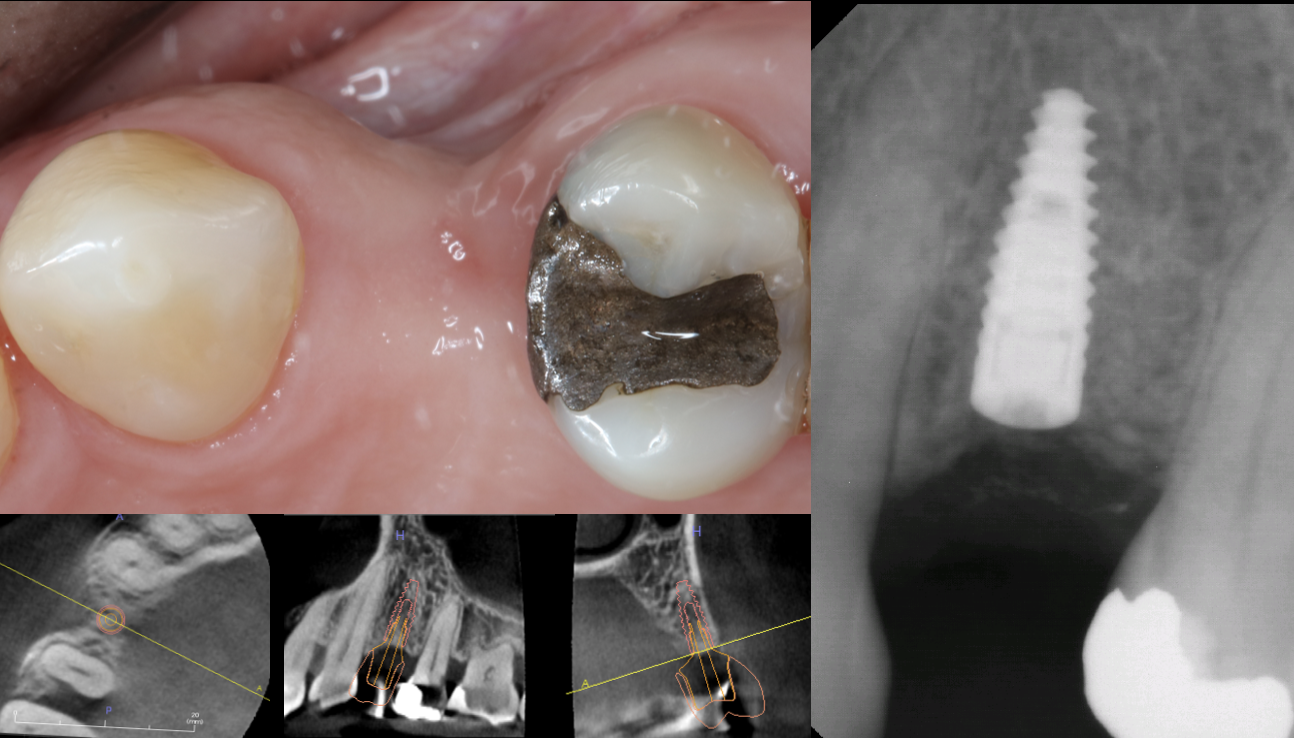

Dental implants have become the most desirable option to replace missing teeth due to their ability to integrate with our bodies and perform as natural teeth. The therapy requires careful study of the existing jawbone, and often times bone grafts are necessary to increase the bone volume to facilitate implant placement.